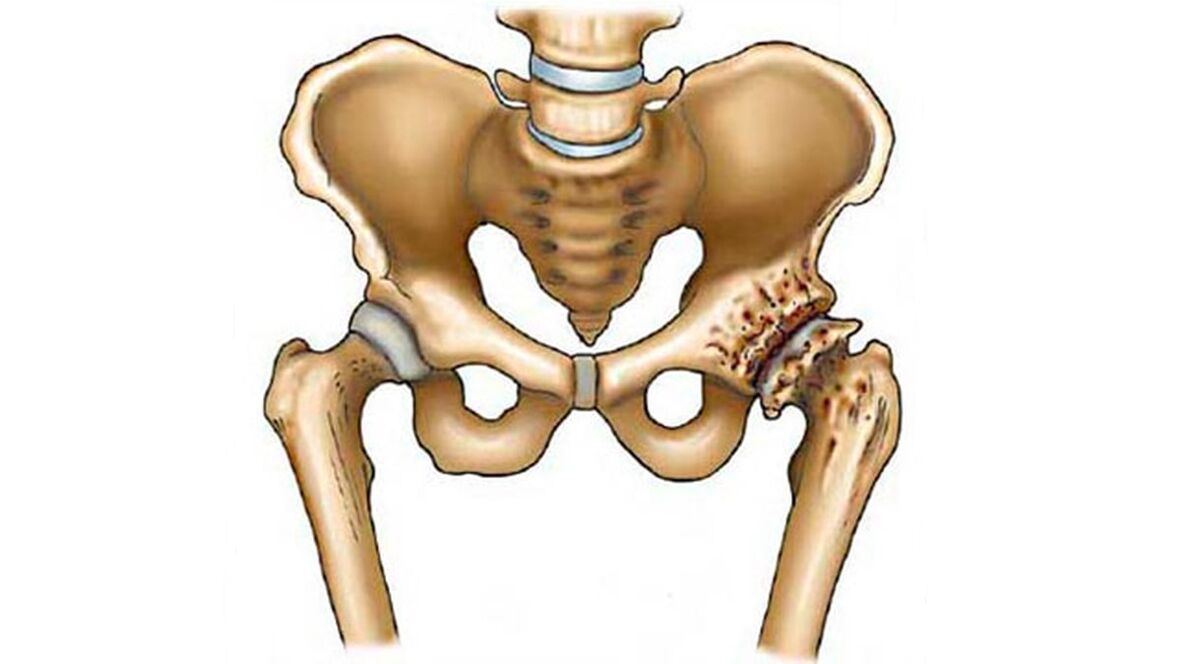

Arthrose ist eine degenerative Erkrankung des Knorpelgewebes, die die Gelenke der Wirbel und alle Knochen des Skeletts befallen kann. Das Hüftgelenk (HJ) ist das größte und am stärksten beanspruchte Knochengelenk. Daher ist die Coxarthrose (deformierende Arthrose des Hüftgelenks) eine sehr häufige Ursache für Behinderungen bei Patienten über 50 Jahren.

Der mit elastischem Knorpel bedeckte Femurkopf liegt in der Hüftpfanne der Beckenknochen.

Es gibt einseitige Läsionen (wenn die Krankheit ein Gelenk betrifft) und bilaterale Läsionen – wenn beide Gelenkflächen der Hüfte betroffen sind.

- Der Knorpel wird dünner, er wird trocken und rau.

- Verdickung des darunter liegenden Knochens, sein seitliches Wachstum.

- Durch überwucherte Osteophyten verschwindet der Gelenkraum praktisch, es kommt zu einer Verschmelzung und einem vollständigen Funktionsverlust des Hüftgelenks.